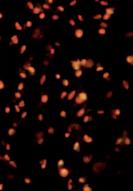

Zdjęcie mikroskopowe "Czy gwiazdy świecą na czerwono?"

przedstawia naturalną śmierć (samobójstwo) komórek raka szyjki macicy Zdjęcie wykonano w Dr Rath Research Institute

Pełna galeria zdjęć jest dostępna pod adresem:

www.dr-rath-humanities-foundation.org/exhibition/index.html

„Czy gwiazdy świecą na czerwono?“